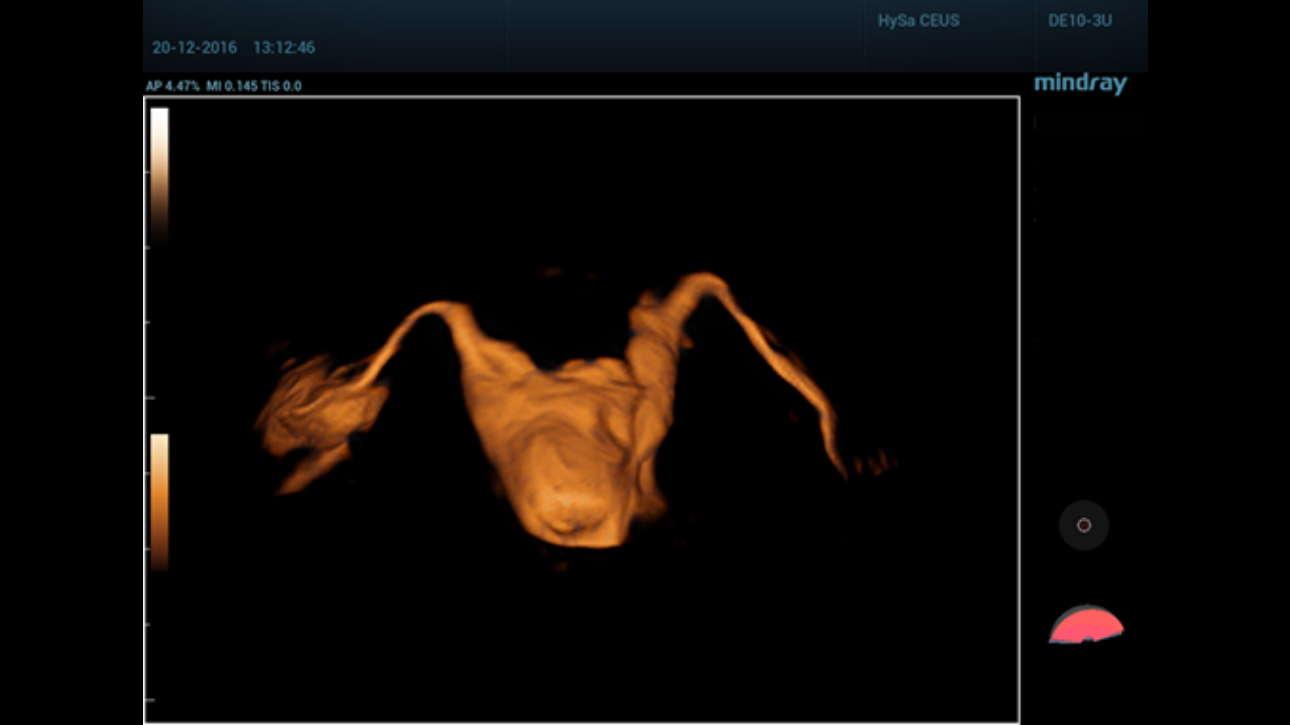

A simple and well-tolerated ultrasound procedure used to assess the patency of the fallopian tubes, as well as detect abnormalities of the uterus and endometrium.